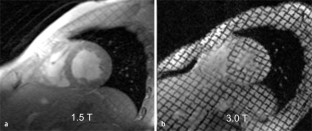

Abb. 1

CAS  PubMed  Article  Google Scholar

27. Gutberlet M, Schwinge K, Freyhardt P et al (2005) Influence of high magnetic field strengths and parallel acquisition strategies on image quality in cardiac 2D CINE magnetic resonance imaging: comparison of 1.5 T vs. 3.0 T. Eur Radiol 15(8):1586–1597

PubMed  Article  Google Scholar